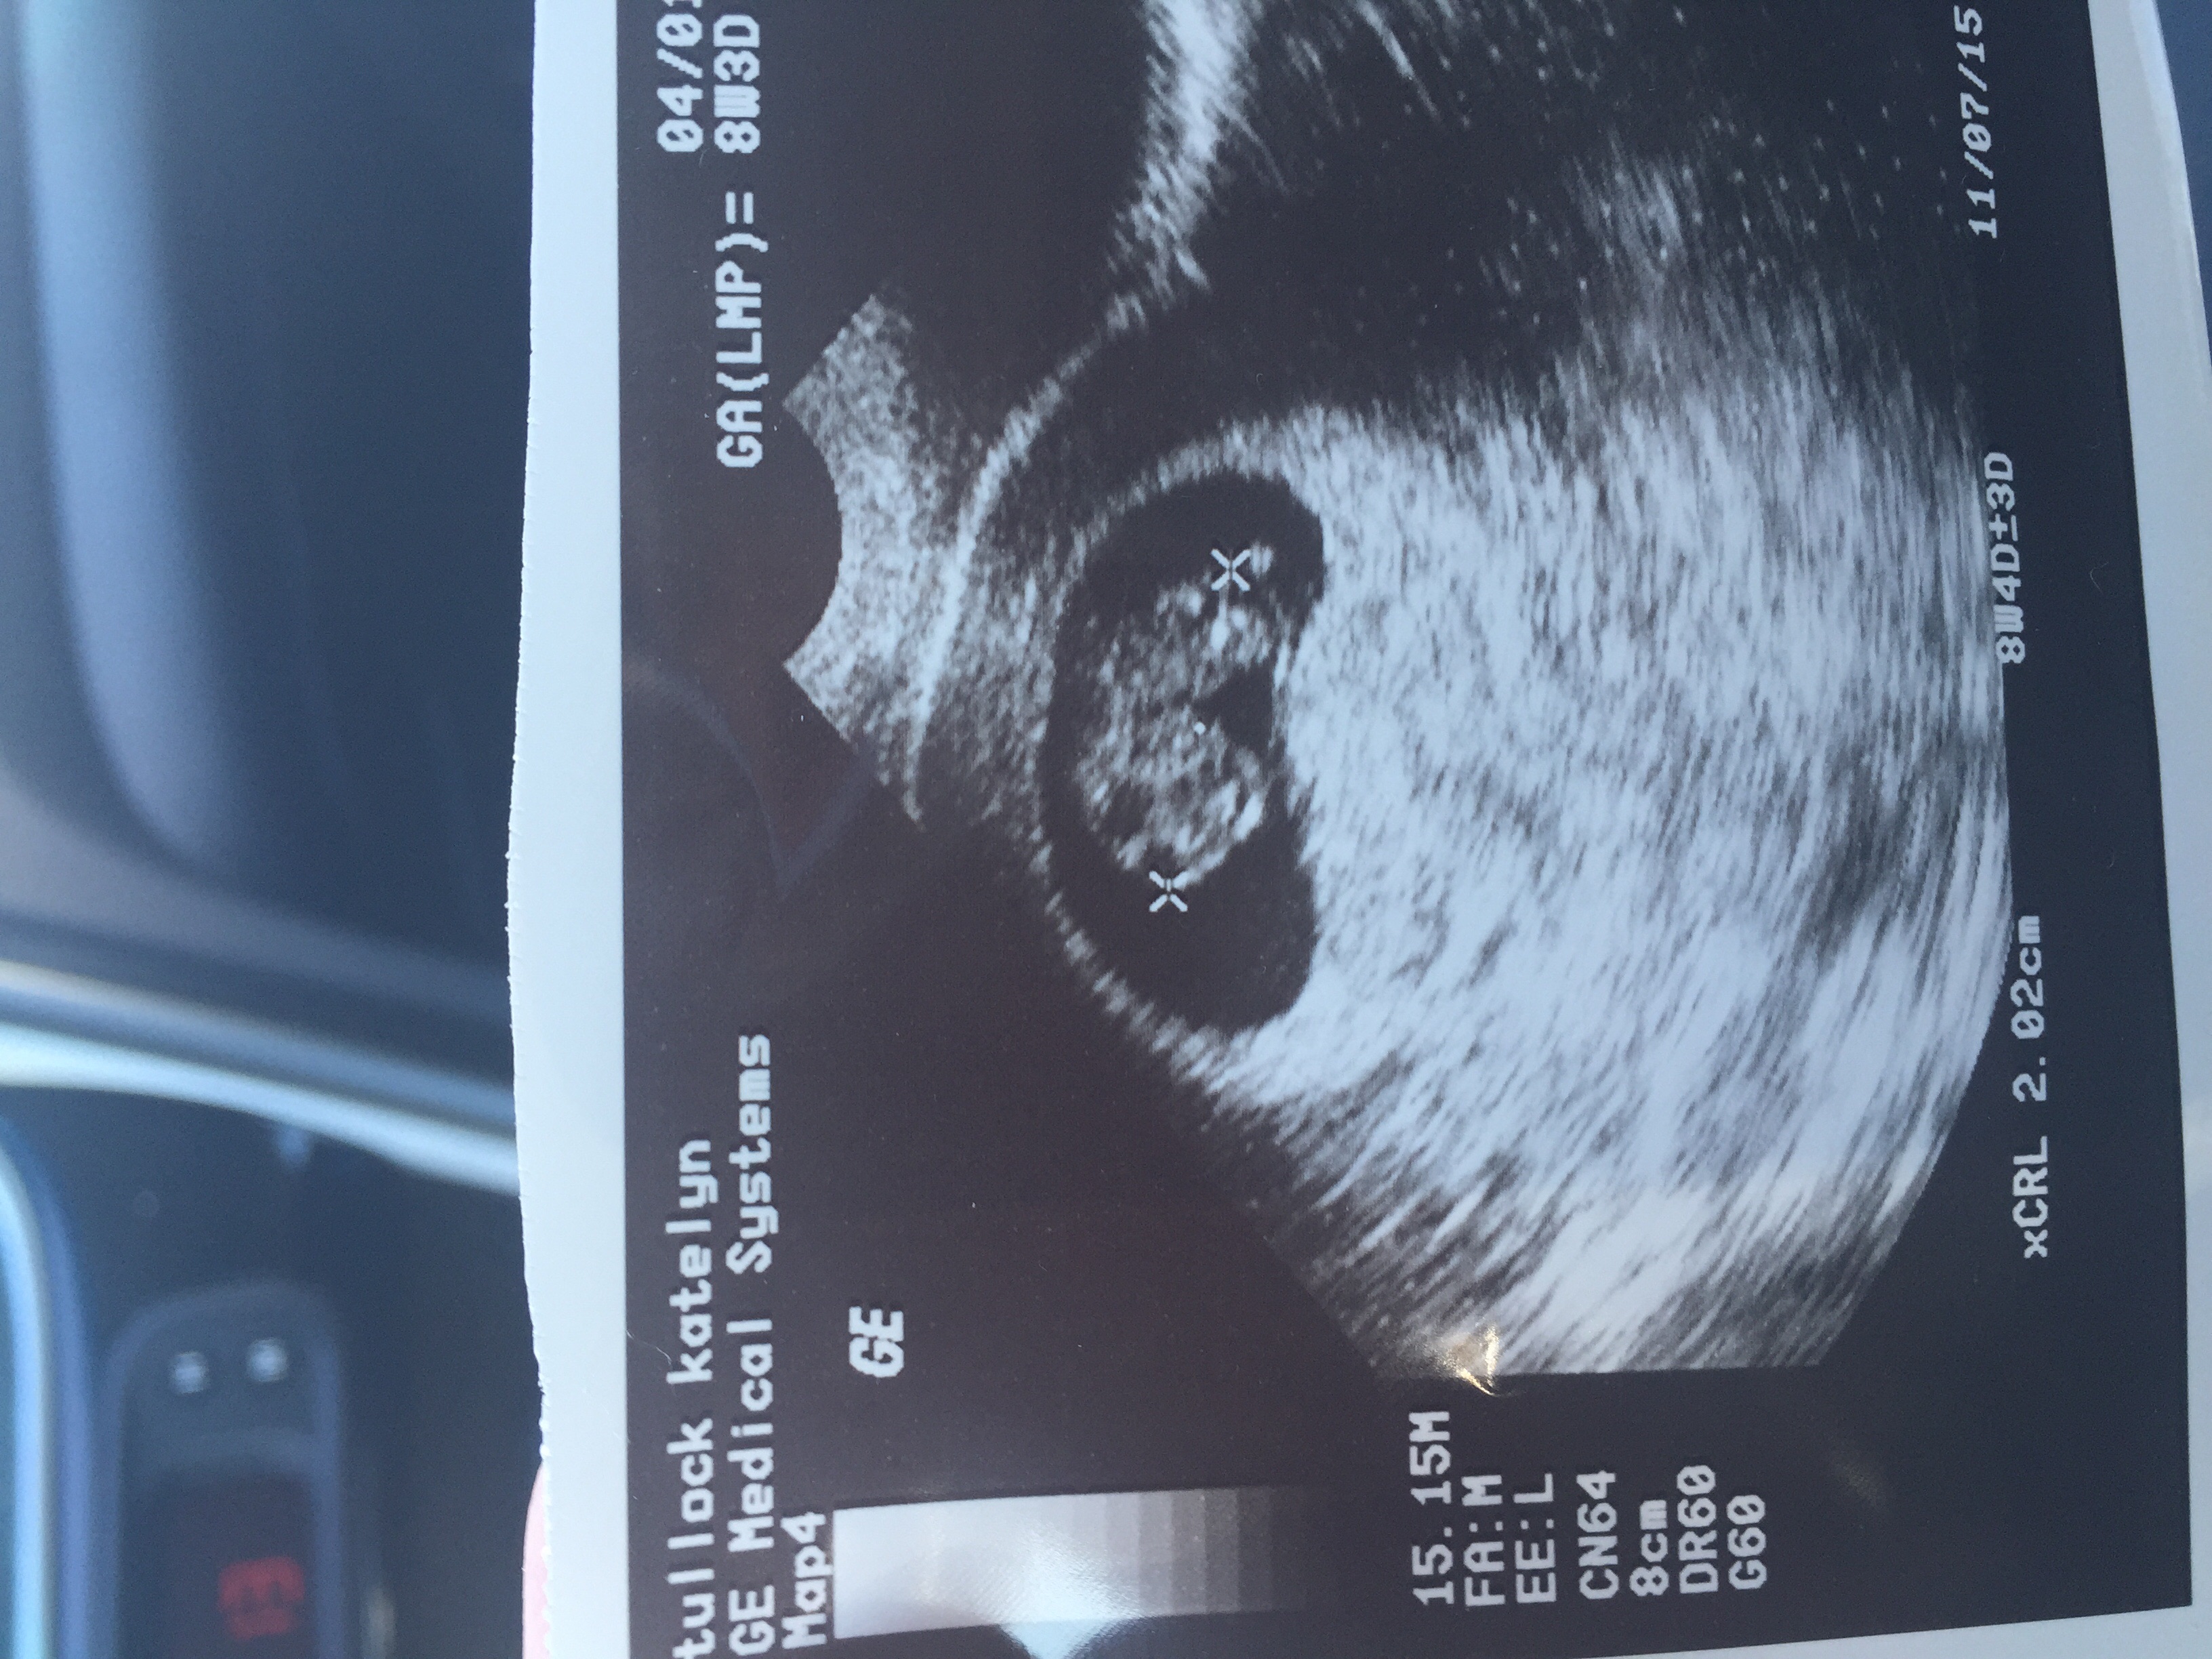

Im so excited to finally post my first ultra sound. Measuring at 8 weeks 2 days ( 4 days earlier than we thought) and having a heartbeat of 168, everything is looking awesome! And our little blob is thriving!